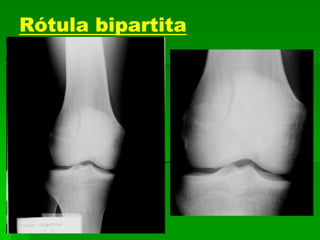

Rótula bipartita

RÓTULA TRIPARTITA